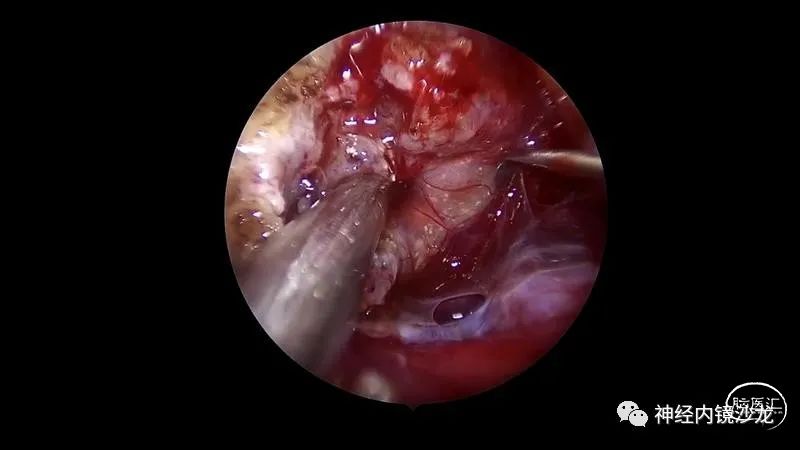

精彩图表

从事神经外科十余年,擅长神经外科肿瘤诊治,尤其是神经内镜微创手术治疗垂体瘤、颅咽管瘤、脑膜瘤等颅底肿瘤